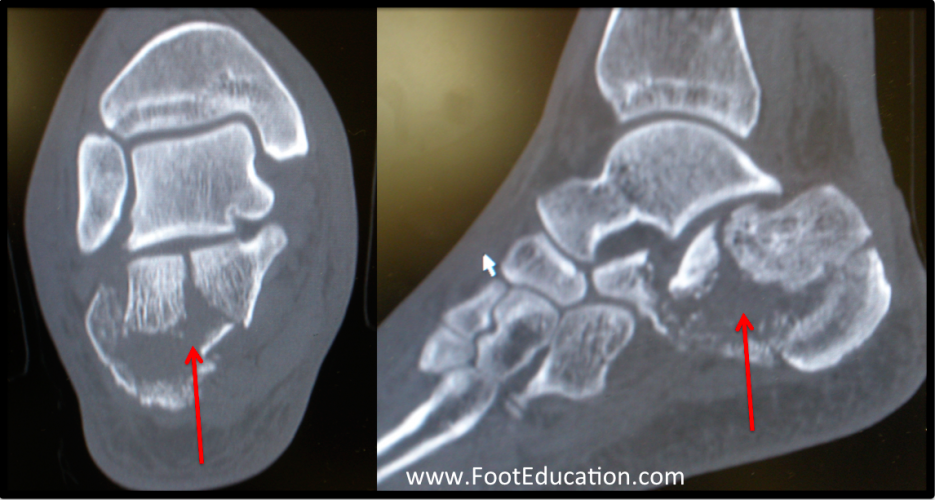

Calcaneus Fracture. Le processus de récupération d'une fracture du calcanéum ou l'os du talon dû à un traumatisme, à une surutilisation chronique ou à une pression récurrente au niveau du talon n'est pas facile et nécessite beaucoup de temps De plus, les forces et mouvements répétitifs, ainsi que l'affaiblissement des os (ostéoporose), peuvent entraîner un type de fracture du calcanéum appelé fracture de stress.

Calcaneus Fractures Trauma Orthobullets. Voici un aperçu général du processus de guérison et. Le processus de guérison peut être divisé en plusieurs phases : Phase initiale : immobilisation et protection du pied pour permettre à l'os de guérir